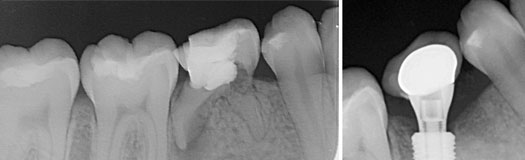

Une molaire du bas perdue serra remplacée par un implant.

Une molaire du haut perdue remplacée par une racine artificielle.